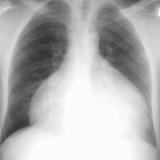

Case 4a

Peric effusion